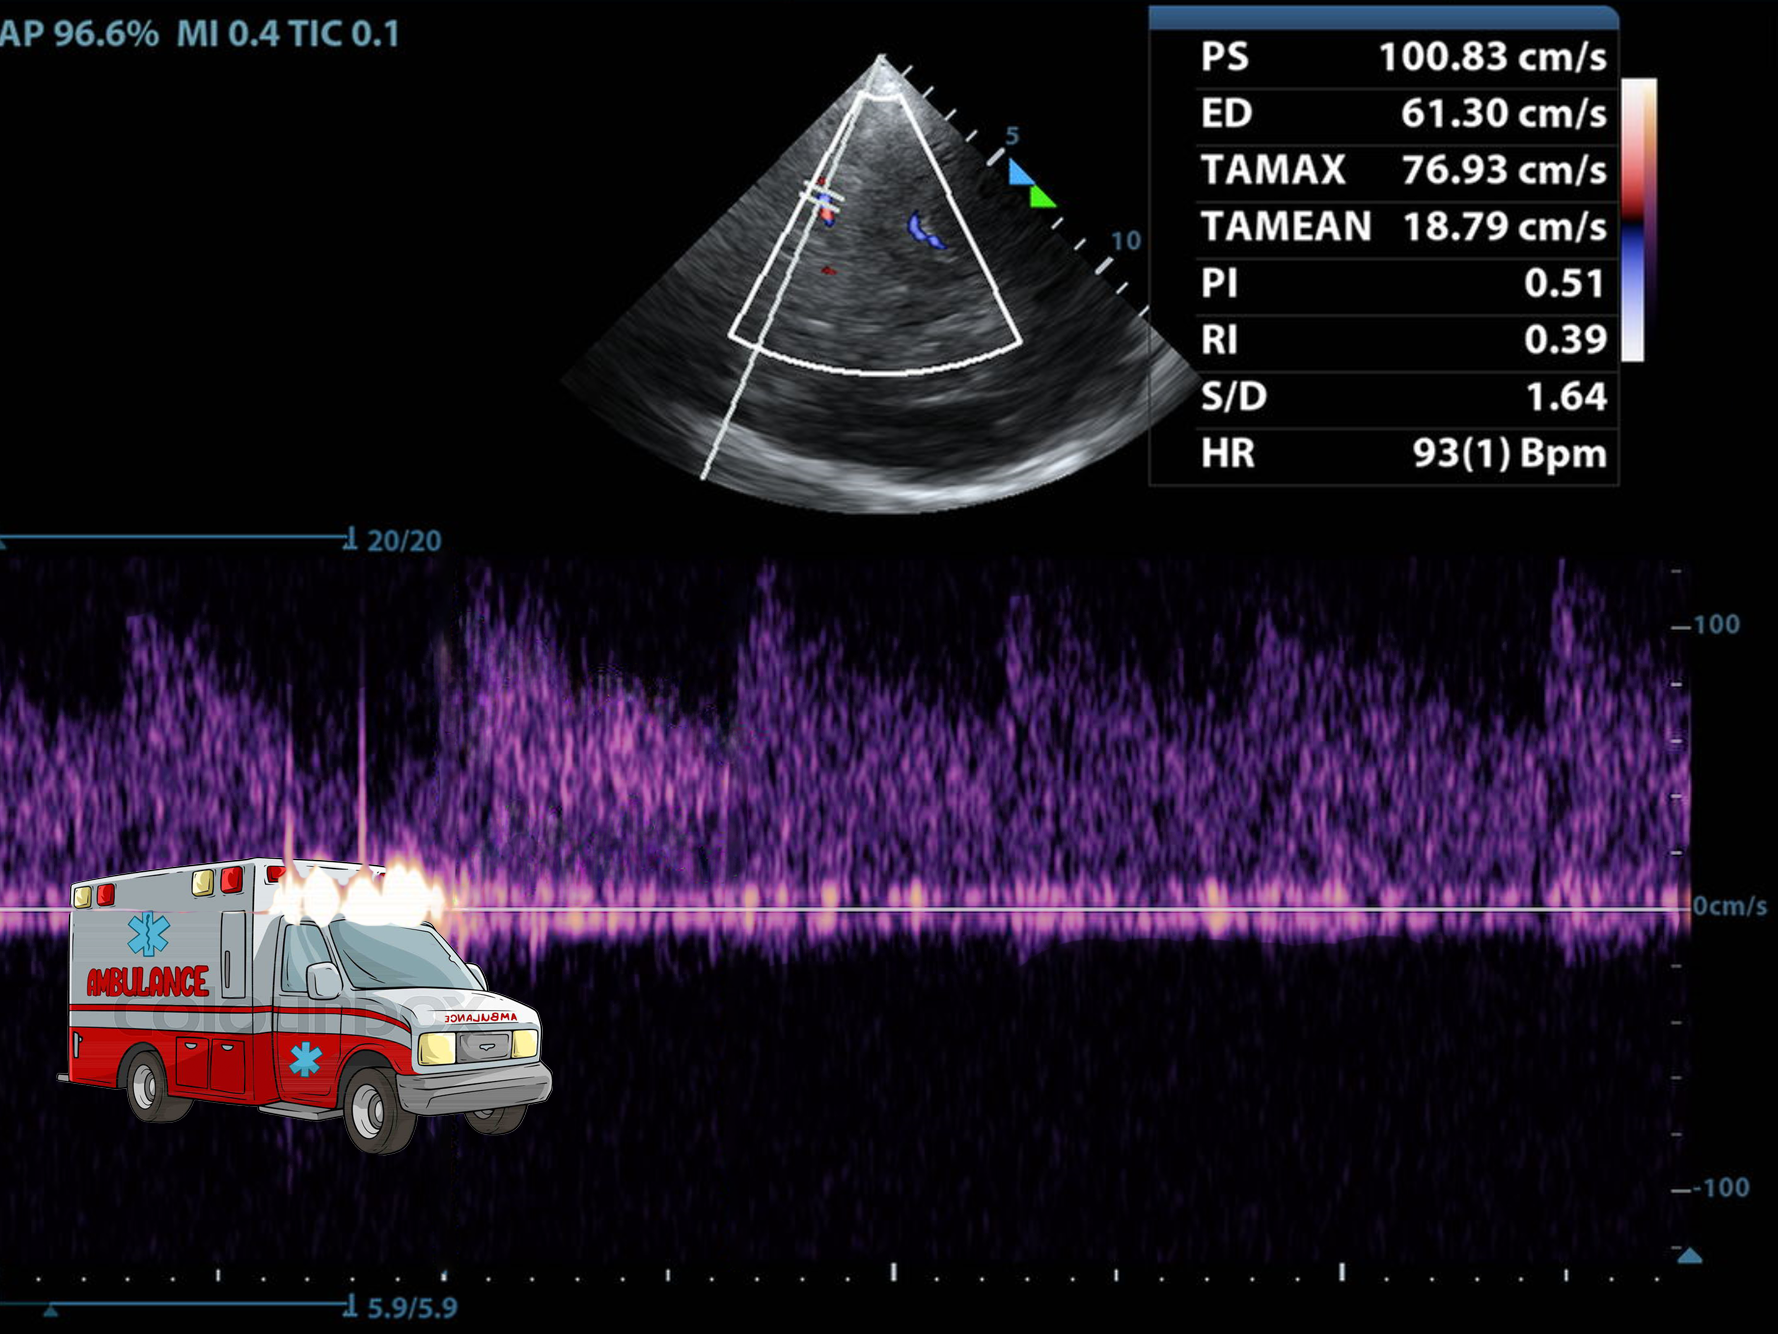

This is the Diencephalon Plane, where the dark thalami surround that sweet, sweet third ventricle like a rain cloud.

This is also where the Circle of Willis lives. But practice getting here first--finding the third ventricle can be challenging.